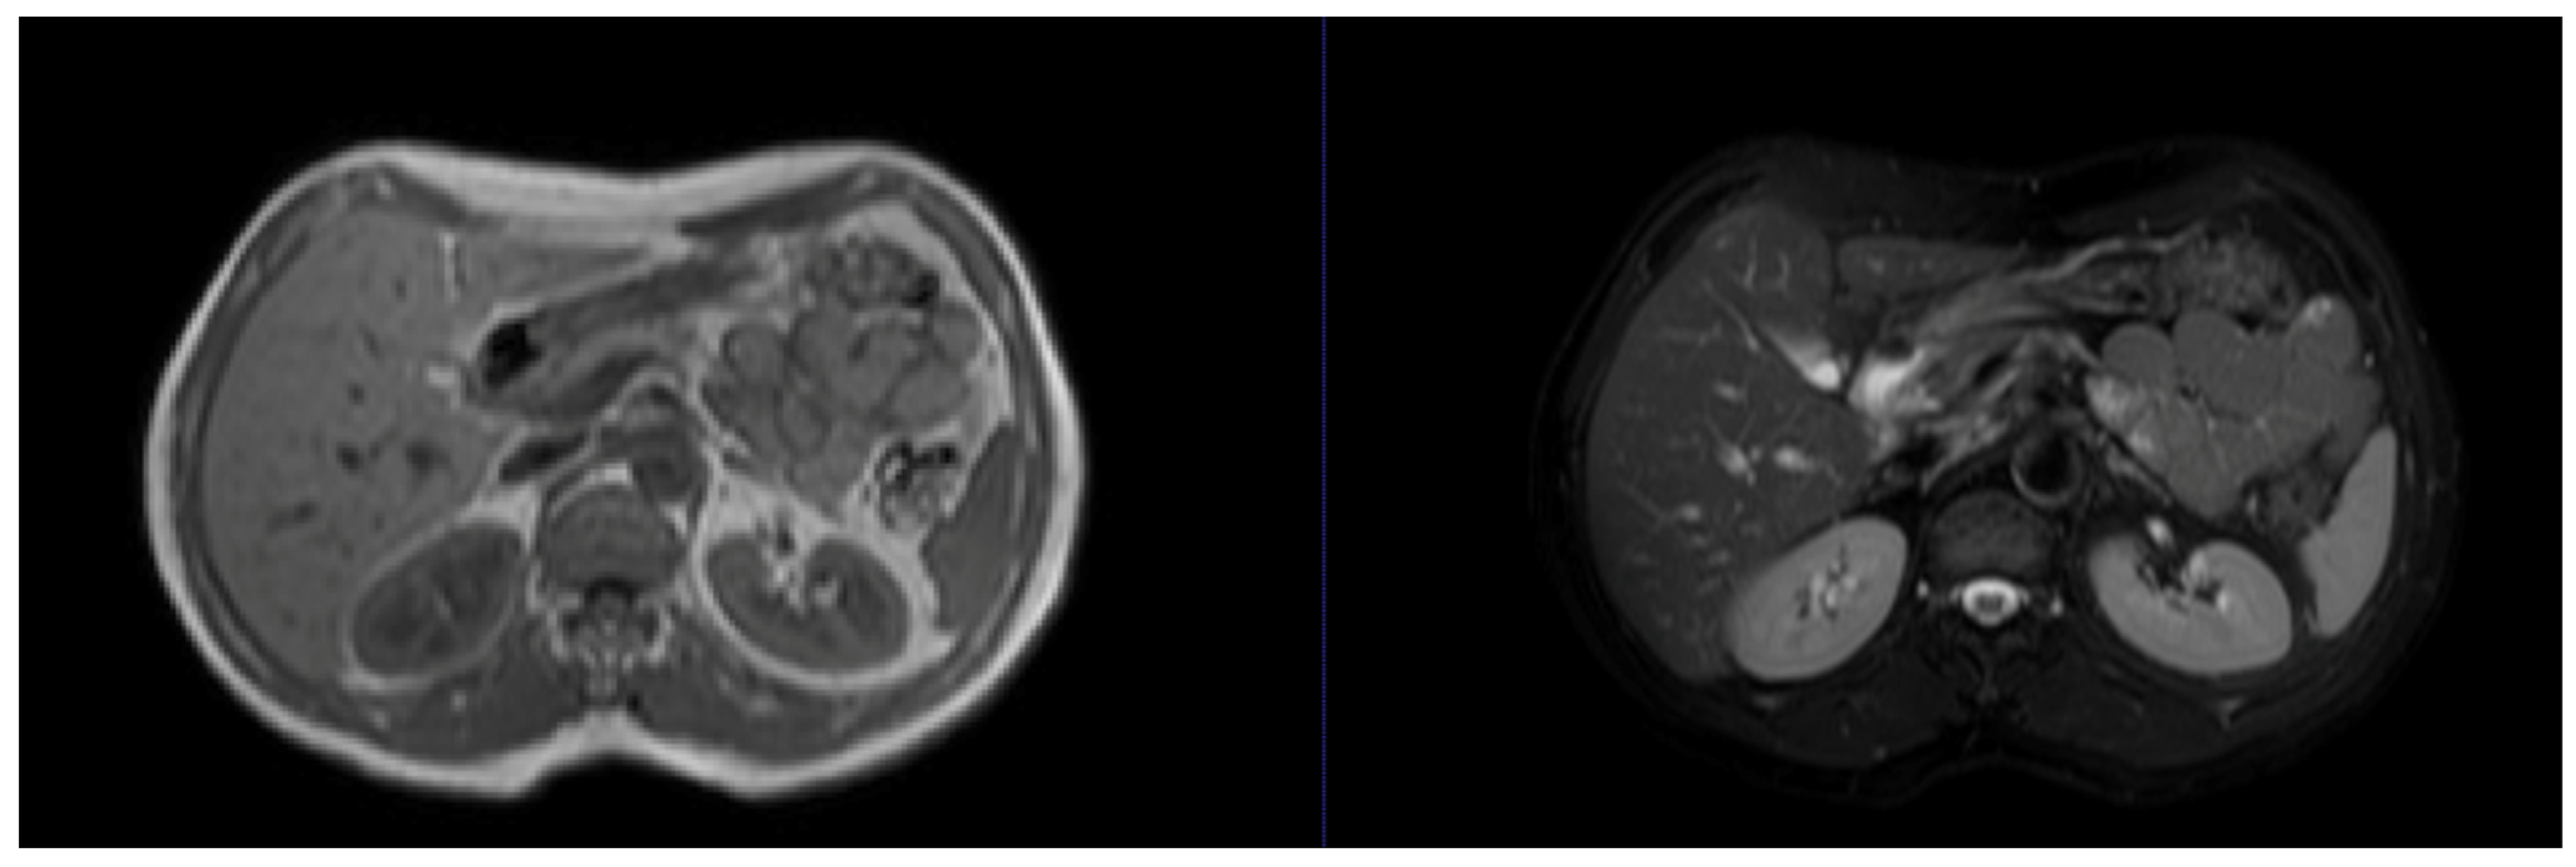

| CHAOS | Abdominal (kidney, liver, and spleen) CT and MRI scans from 80 patients in DICOM format with ground-truth masks annotated by certified radiologists | Promotes multi-modality imaging research and provides data on healthy organs that are useful for benchmarking | Small sample and lack of pathological information, may be insufficient for model training for pathology detection |